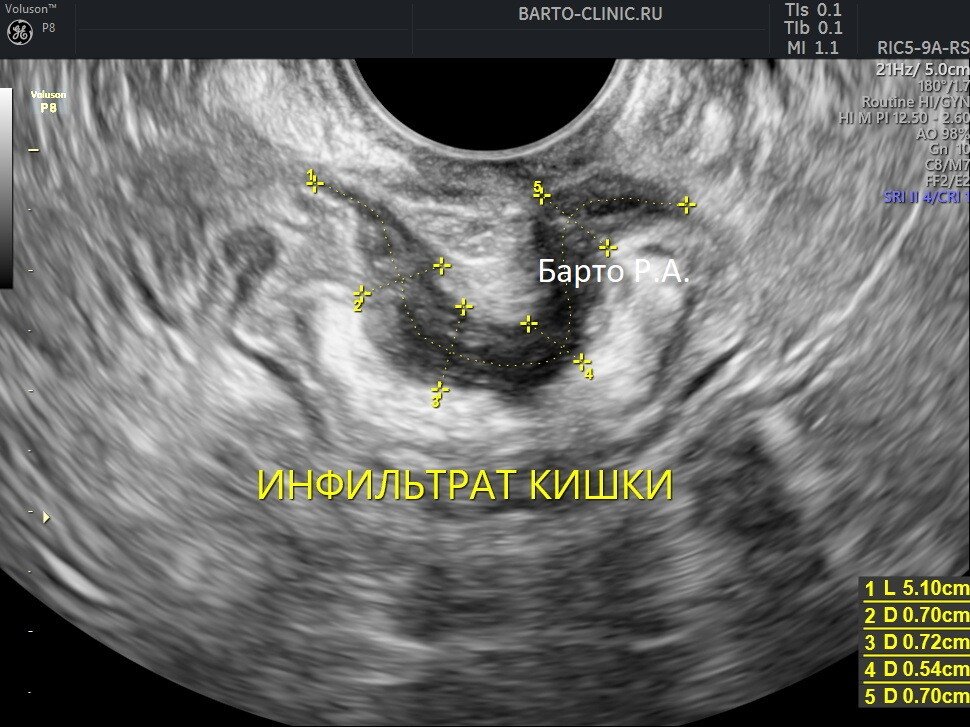

Узи покажет эндометриоз

Узи покажет эндометриоз 110 фото